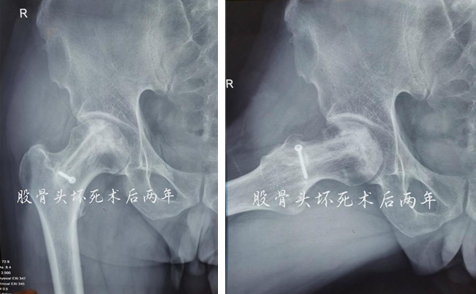

术后两年

术后12个月和24个月,患者来院复查,影像片子显示患者右侧股骨头髋臼平整光滑,股骨头圆润光滑,股骨头内骨小梁密度均匀,已恢复至正常股骨头状态,几乎与正常人股骨头无异。患者随访时说:“来财神捕鱼 之前,我独立行走都困难,短短几米的距离,我可能要花费三四分钟才能走完。手术之后,我不仅可以健步如飞,还能做下蹲等动作,也不必担心重体力劳动导致股骨头无法承受的问题,这个手术真的是太好了,不仅救了我,也救了我一家人……”